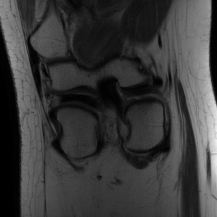

| Ground Truth | LORAKI | Global | LONDN-MRI | LONDN-MRI | Oracle |

| (1 iteration) | (2 iterations) | ||||

![]() |

| PSNR = dB | PSNR = 33.17 dB | PSNR = 35.10 dB | PSNR = 35.67 dB | PSNR = 35.74 dB | PSNR = 35.87 dB |